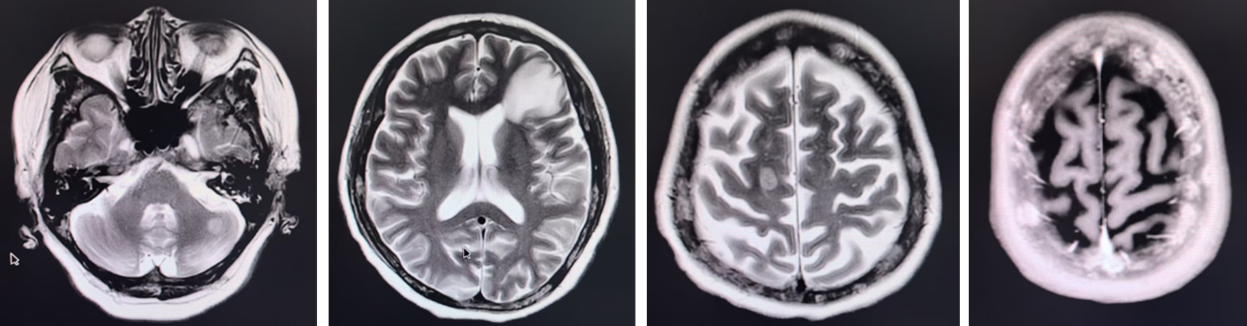

2025年8月,患者出现脑部多发转移(额叶、小脑及颅骨)。在完成颅内放疗后,基于其PIK3CA突变及扩增背景,考虑到患者基础情况较差,无法耐受化疗,且既往激素受体存在表达,参考INAVO120研究治疗模式,医疗团队果断采取联合靶向策略。